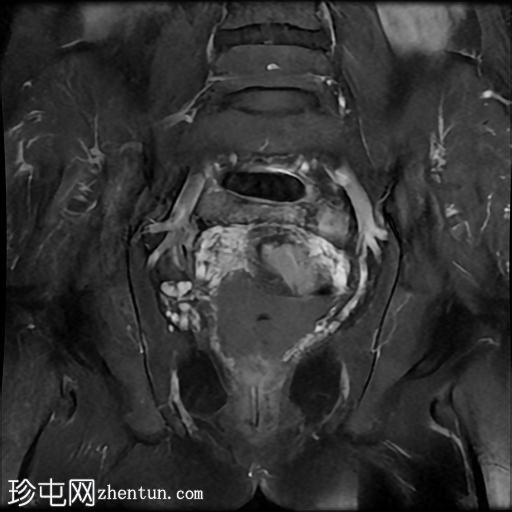

冠状位T2加权像

脂肪抑制像

该宫颈癌体积较大,局部晚期,大小为22 x 40 x 42 mm,起源于宫颈左后外侧壁,向下延伸至阴道上三分之一处,位于宫颈中后外侧壁。

病变还累及左侧前外侧的宫旁组织。

左侧髂内静脉分叉下方可见一异常信号淋巴结肿大,最大短轴直径(SAD)为 8 mm。该淋巴结在弥散加权成像(DWI)上显示水限制,并有对比增强。